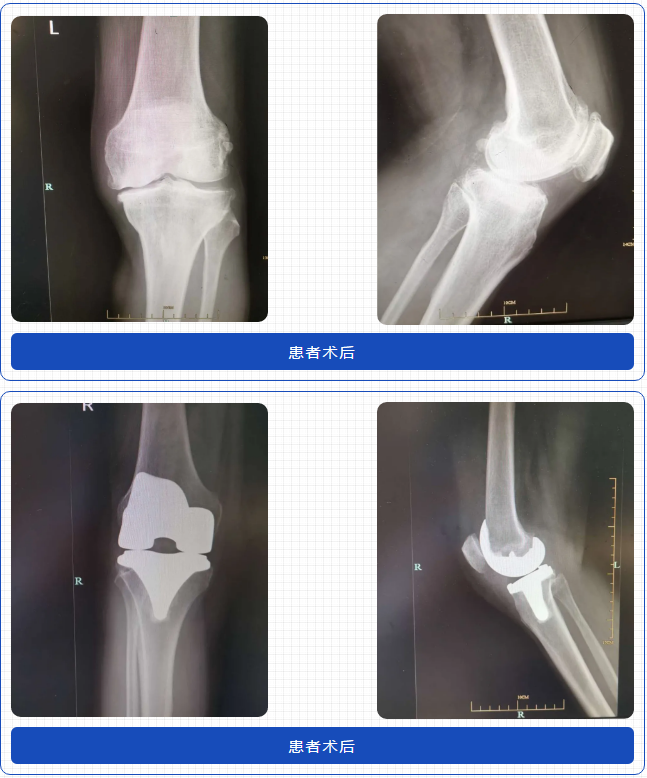

學(xué)術(shù)分享完成后,馬上帶領(lǐng)學(xué)員開(kāi)展三臺(tái)換膝和一臺(tái)換強(qiáng)直髖手術(shù)的現(xiàn)場(chǎng)教學(xué)。孫院長(zhǎng)憑借嫻熟的技術(shù)平時(shí)十幾分鐘就可以完成一臺(tái)換髖手術(shù),而在手術(shù)教學(xué)現(xiàn)場(chǎng),孫院長(zhǎng)循循善誘引導(dǎo)在場(chǎng)的醫(yī)生思考,耐心講解每個(gè)步驟和技術(shù)難點(diǎn)及解決方案。孫院長(zhǎng)像一盞燈一樣,把自己精湛技術(shù)毫無(wú)保留的教授給大家,彰顯了一位大師醫(yī)者的博大胸懷,令同行敬仰。